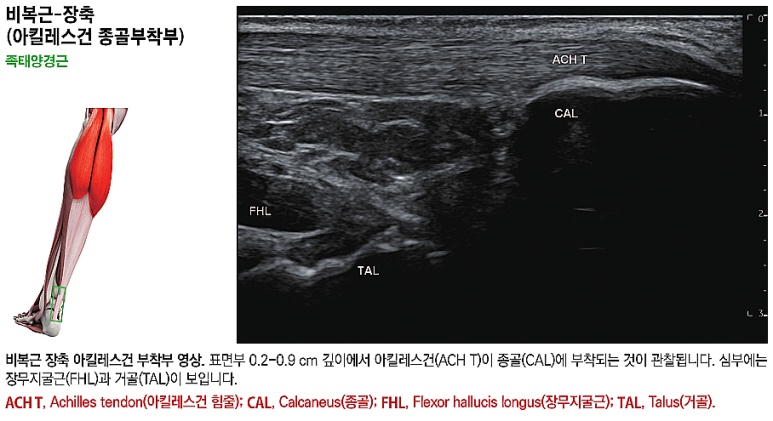

경혈초음파, 아킬레스건

족태양경근

위 그림은 제가 출판한

초음파 전공 서적인데요.

혈자리를

손 끝 감각을 이용해 먼저 찾고

초음파로 다시 체크합니다.

영상에서

족태양경근은 깊이에 따라

아킬레스건, 장무지굴근, 종골, 거골 등

다양한 구조물이 보입니다.

그 중에

아킬레스건(ACH T)은흰색 줄무늬 섬유 패턴으로보이는데요.